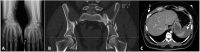

Mesenteric laceration is an uncommon cause of hemoperitoneum, with nonspecific signs and symptoms and frequently is camouflaged by the signs of other traumatic lesions. There is a high risk to go unnoticed increasing morbidity and mortality. We report a case of a 43-year-old man, who was involved in a motorcycle accident, with thoraco-abdomino-pelvic trauma, but without evidence of intra-abdominal lesions on exams, with exception of hemoperitoneum. Due to hemodynamic instability, it was performed an exploratory laparotomy. Intraoperative findings were mesenteric lacerations affecting a small bowel segment. This case demonstrates that a high index of suspicion is necessary to diagnose and treat lesions like mesenteric laceration, not visible early on imaging but potentially fatal, with high risk of complications.